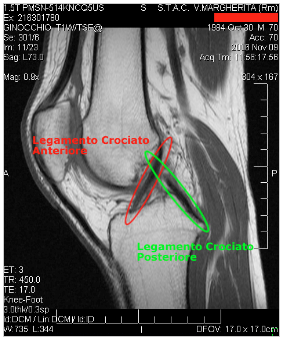

COME AVVIENE - La distorsione al ginocchio avviene attraverso un movimento anomalo dell’articolazione che viene ruotata oltre i limiti articolari e non provoca lacerazioni della cute. Il movimento di rotazione è rapido e violento e non provoca fratture ossee ma può portare allo stiramento o alla lesione parziale o totale dei legamenti che mantengono stabile l’articolazione, generando gonfiore e dolore locale.

E’ importante subito dopo la presenza di questi sintomi una visita ortopedica specializzata o nei casi estremi degli esami radiologici (TAC- RMN), perché se non valutata e curata in tempo con tutte le accortezze possibili, può portare alla limitazione funzionale dell’articolazione. Anche la distorsione del ginocchio, come quella della caviglia, ha una sua scala di gravità che va dalla semplice lesione di alcune fibre alla rottura completa del legamento; esse vengono divise in tre tipi di lesioni:

terzo grado: provoca la rottura totale del legamento crociato anteriore (LCA), legamento collaterale mediale (LCM), legamento crociato posteriore (LCP) poco frequente.

Le distorsioni dell’LCA sono provocate da un arresto improvviso seguito da una torsione interna, esterna; da una forte iperestensione o da un trauma violento al compartimento esterno del ginocchio. La lesione del LCP è una conseguenza di un trauma diretto al compartimento anteriore del ginocchio mentre la lesione del LCM è provocata anch’essa da un forte trauma però nella regione interna del ginocchio in atteggiamento varo.